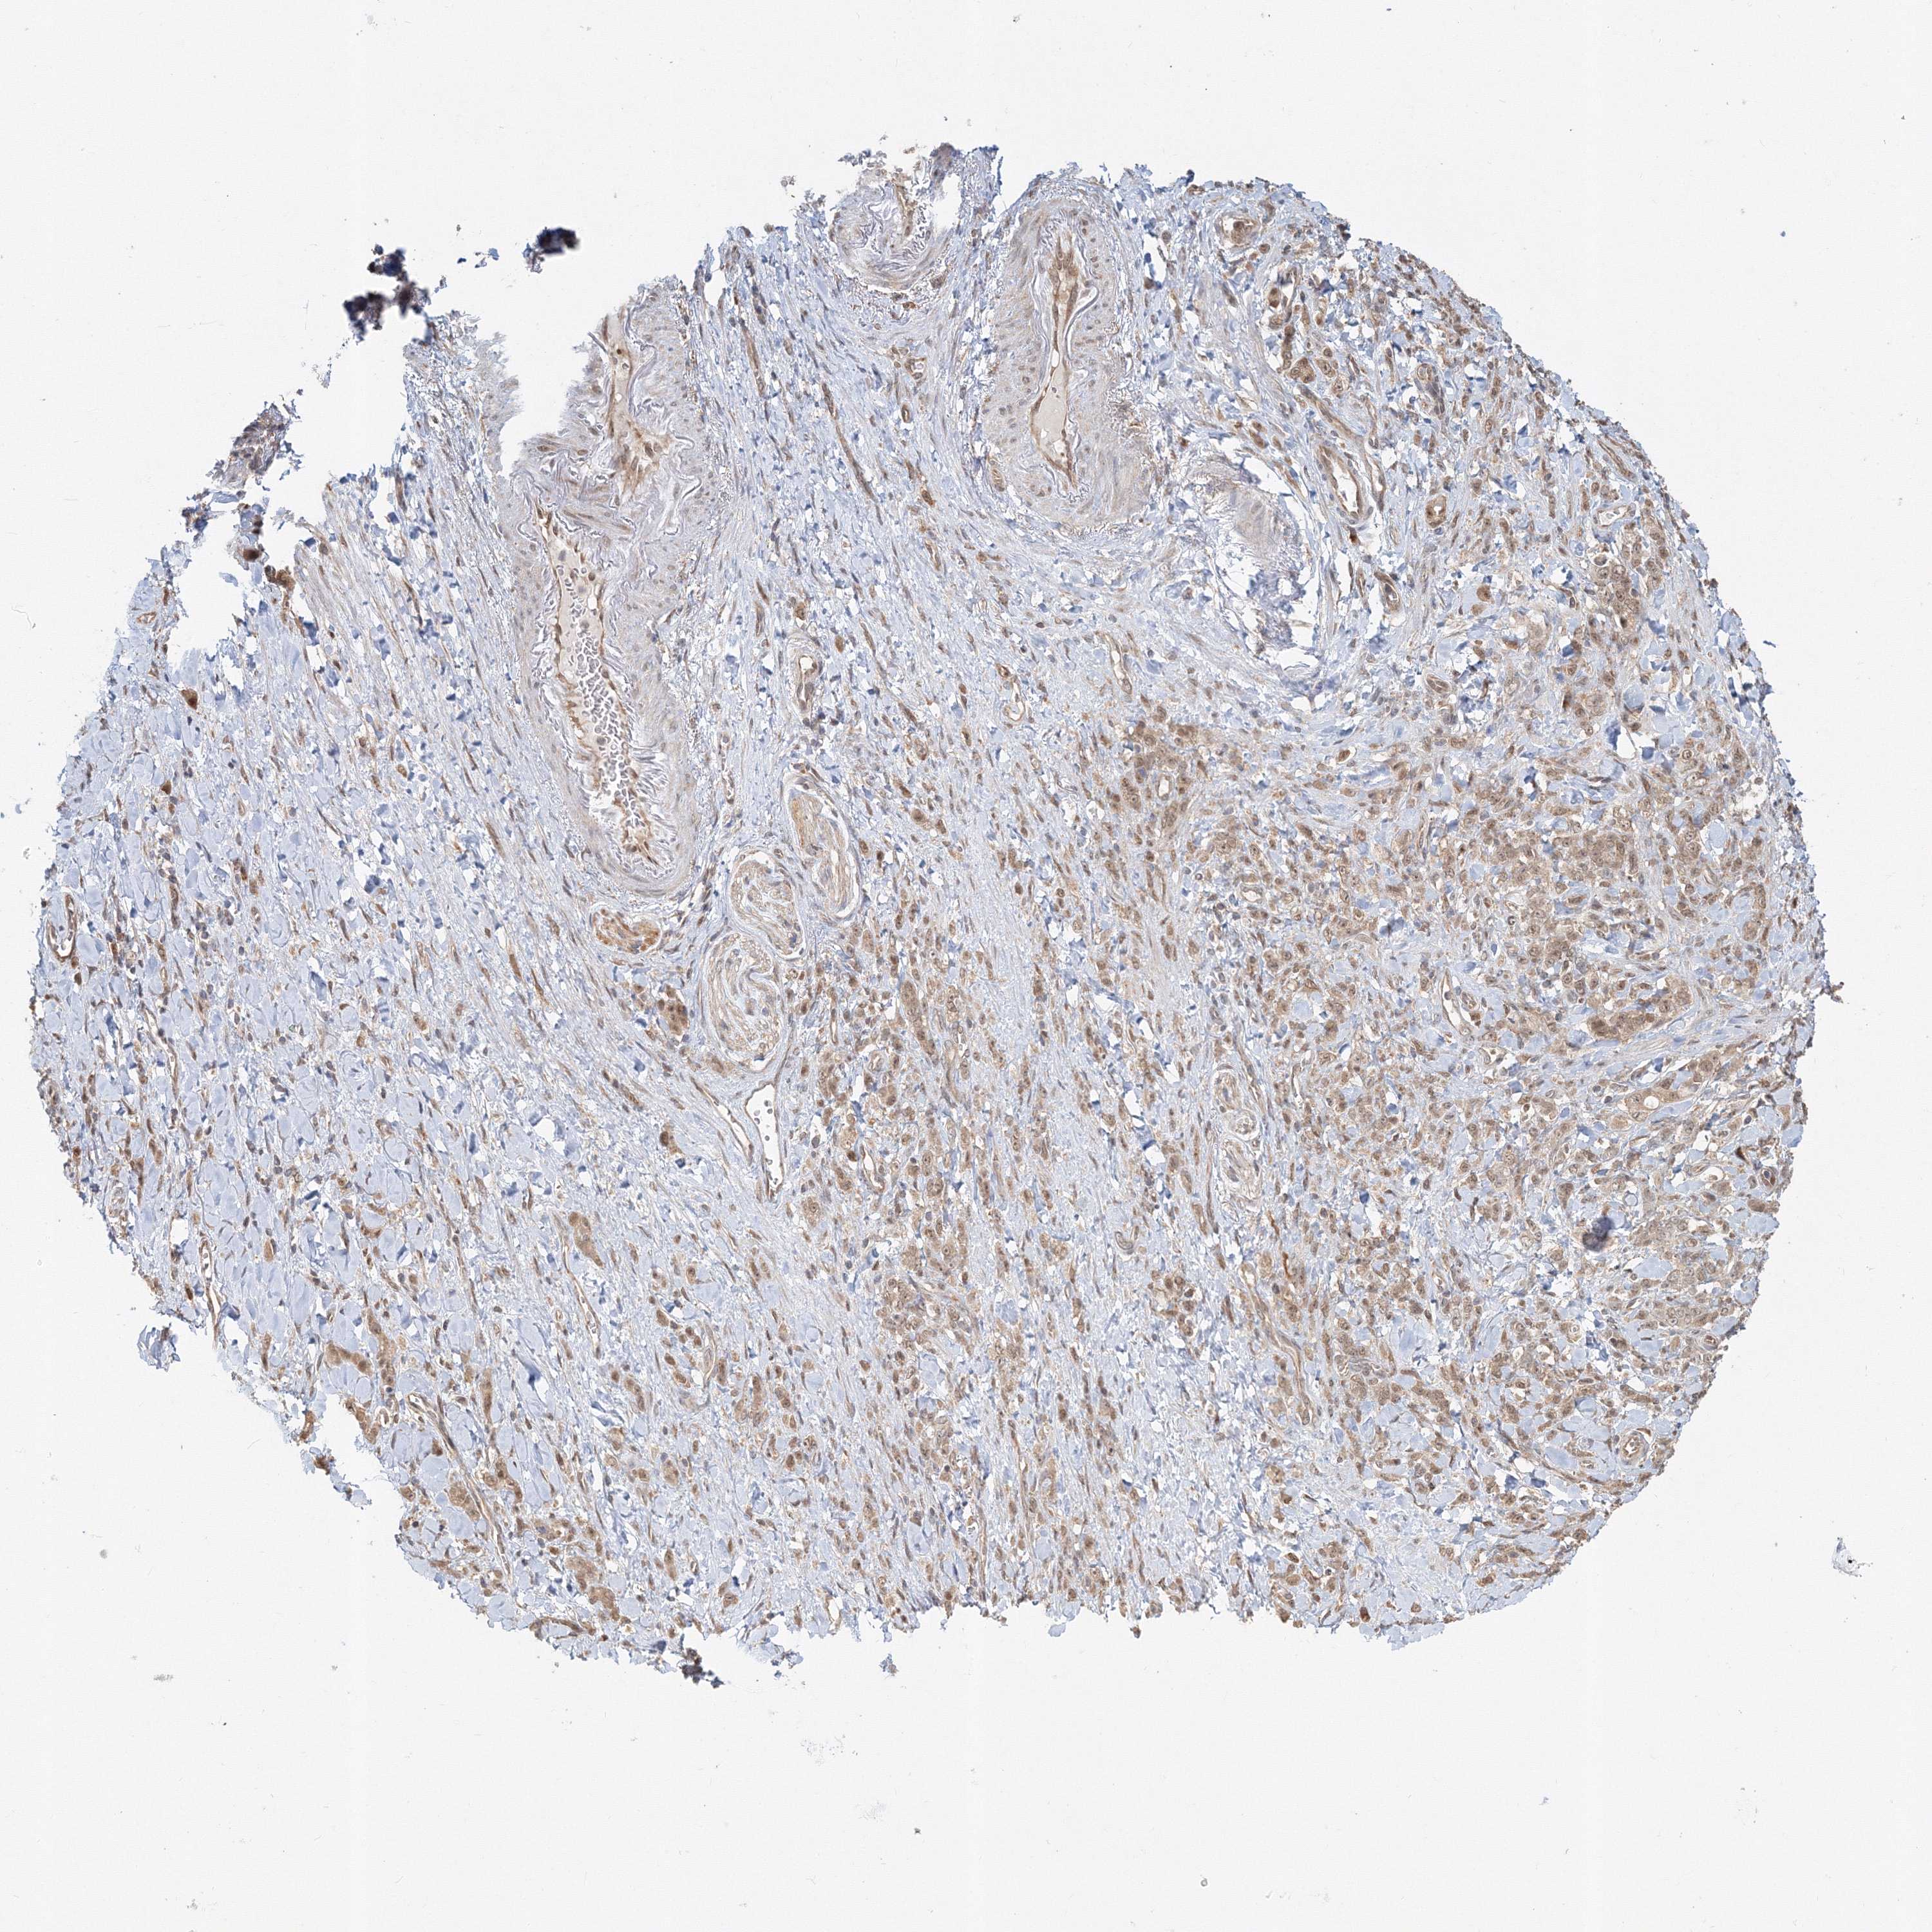

STOMACH CANCER - Protein expressioni

A mouse-over function shows sample information and annotation data. Click on an image to view it in a full screen mode. Samples can be filtered based on level of antibody staining by selecting one or several of the following categories: high, medium, low and not detected. The assay and annotation is described here.

Note that samples used for immunohistochemistry by the Human Protein Atlas do not correspond to samples in the TCGA dataset.

Antibody stainingi

Antibody staining in the annotated cell types in the current human tissue is reported as not detected, low, medium, or high, based on conventional immunohistochemistry profiling in selected tissues. This score is based on the combination of the staining intensity and fraction of stained cells.

Each image is clickable and will lead to virtual microscopy that enables deeper exploration of all samples and also displays staining intensity scores, fraction scores and subcellular localization as well as patient and tissue information for each sample.

Antibody HPA036921

Antibody HPA036922

Staining

High

Medium

Low

Not detected

Intensity

Strong

Moderate

Weak

Negative

Quantity

>75%

75%-25%

<25%

None

Location

Nuclear

Cytoplasmic/membranous

Cytoplasmic/membranous,nuclear

Adenocarcinoma, NOS